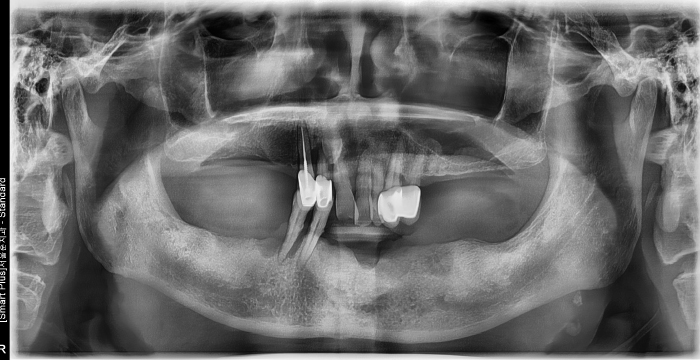

즉시 식립 임플란트 전후 사례

• 식립 전

식립 전

진단 / 3차원 CT / T-Scan교합 분석

서울바른훈치과는 임플란트 전문의 서울대 출신 이상훈 대표원장님이 직접 상담합니다. 3차원 CT분석으로 임플란트 식립 부위의 각도를 파악, 정확한 뼈의 상태를 진단합니다. T-Scan(교합분석장비)를 통해 치아와 치아 사이의 0.01mm의 미세한 오차를 분석합니다.